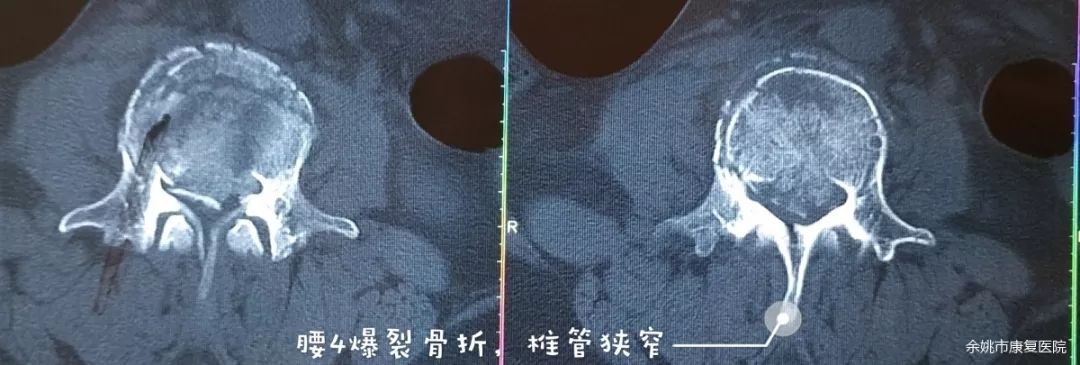

患者毛某某,女,44岁,今年8月初的某一天不慎从二楼高处跌落,当即出现腰部剧痛,双下肢活动障碍,大小便失禁,被送至宁波某医院就诊,诊断“腰4爆裂性骨折,腰1椎体压缩性,脊髓损伤,马尾神经损伤”,即我们常说的胸腰椎骨折伴截瘫。4天后行“前后路胸腰椎切开复位内固定植骨融合术”。